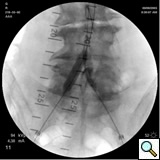

- Simple iliac TASC type A lesions are treated with balloon angioplasty using .035-inch compatible angioplasty balloons with diameters of 5-10 mm and lengths between 20-40 mm. In distal aortic or bifurcation disease, a kissing balloon approach may be necessary (Figure 1). Indications for stenting include suboptimal results of angioplasty with residual gradients, extensive dissection, total occlusion, reoccurrence after angioplasty, ostial location, severe calcification as well as aneurysms. Most commonly balloon expandable stents are used that offer greater radial force, and greater precision for placement for ostial and calcified lesions. More flexible self-expanding stents offer better taper for longer lesions, and are used for antegrade approach, treatment of external iliac and common femoral lesions, and longer lesions. Finally stent grafts are commonly used for aneurysmal pathologies or vascular ruptures.

![]() |

| Figure 1: Kissing balloon for proximal common iliac disease. |